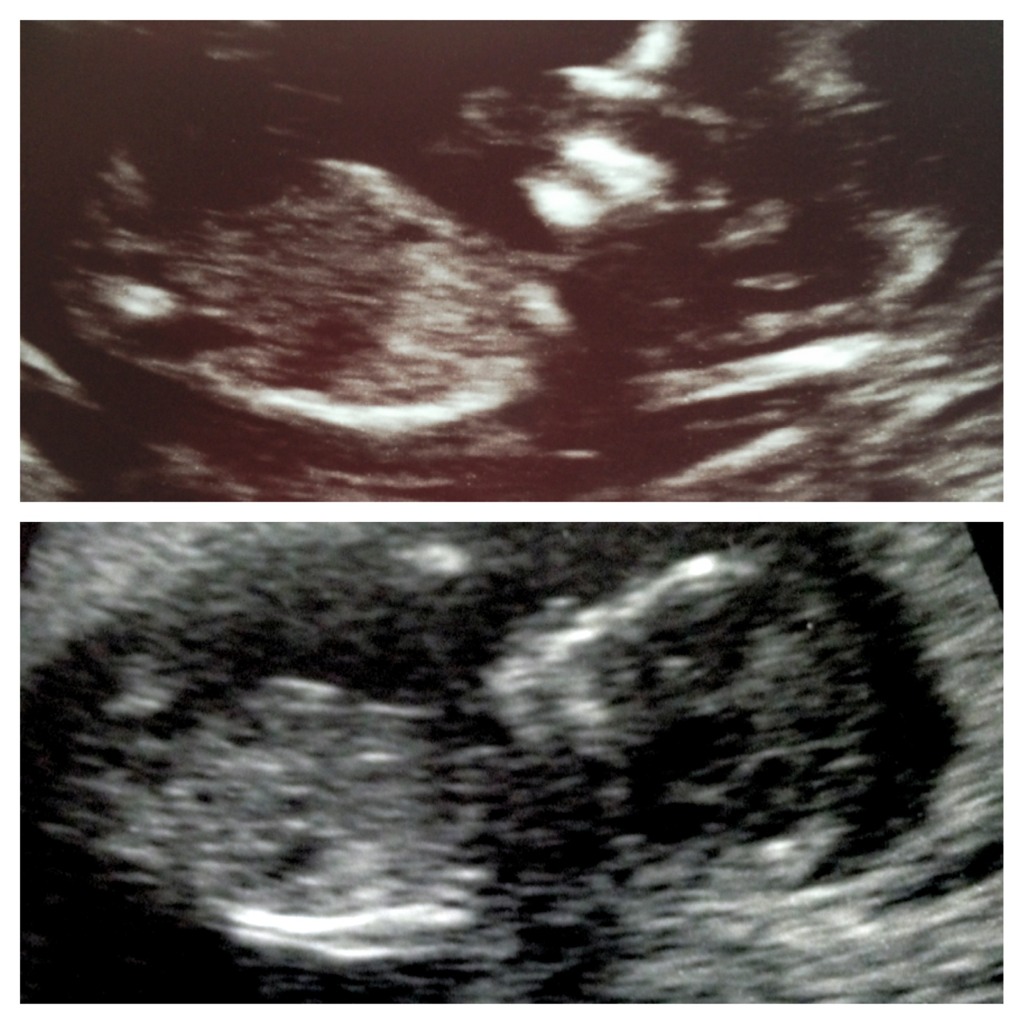

Ok -so I can't stop staring at my 12 wk, 5 day scan. I have asked ynwa if I can use one of her pics to compare to mine (hers is confirmed girl). Ynwa's little one is on top and mine is on the bottom. I'm posting them regular and then also posting one where the nubs are circled. Please help my craziness LOL! My gender scan is on Dec 1st!!!!

Attachment 6386

Attachment 6387